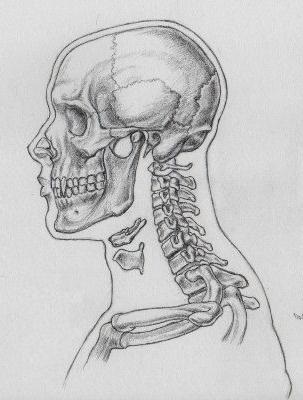

nyakszirti közös

Koponya, anatómia, amely lehetővé teszi neki, hogy készítsen elsősorban a védelmi funkció, akkor is végezze el a különböző mozgásokat, köszönhetően a közös összekötő nyakszirtcsontba és az első csigolya (atlasz). A mellékhatások együttes alkotja a nyakszirti ízfelszínekkel; ez egy pár (mert a két csatlakozik a condylus izületi fossae Atlas) ellipszoid, a membrán két (első és hátsó) és oldalsó szalagok.

Jellemzői a szerkezet a koponya fiatal korban

Az emberi test növekszik és fejlődik akár 20-25 év. Eddig a pontig van egy típusú koponya vegyületek synchondrosis képződött rostos porc. Jelen van a ékalakú és a nyakszirtcsontba, valamint a között, a négy része a nyakszirtcsontba. Az alapja a koponya tartalmaz köves-occipitalis synchondrosis, és egy réteg porcszövet találkozásánál os sphenoidale és rácsszerkezet. Idővel a saját helyén alakul ki a csont, és úgy tűnik, syndesmosis.